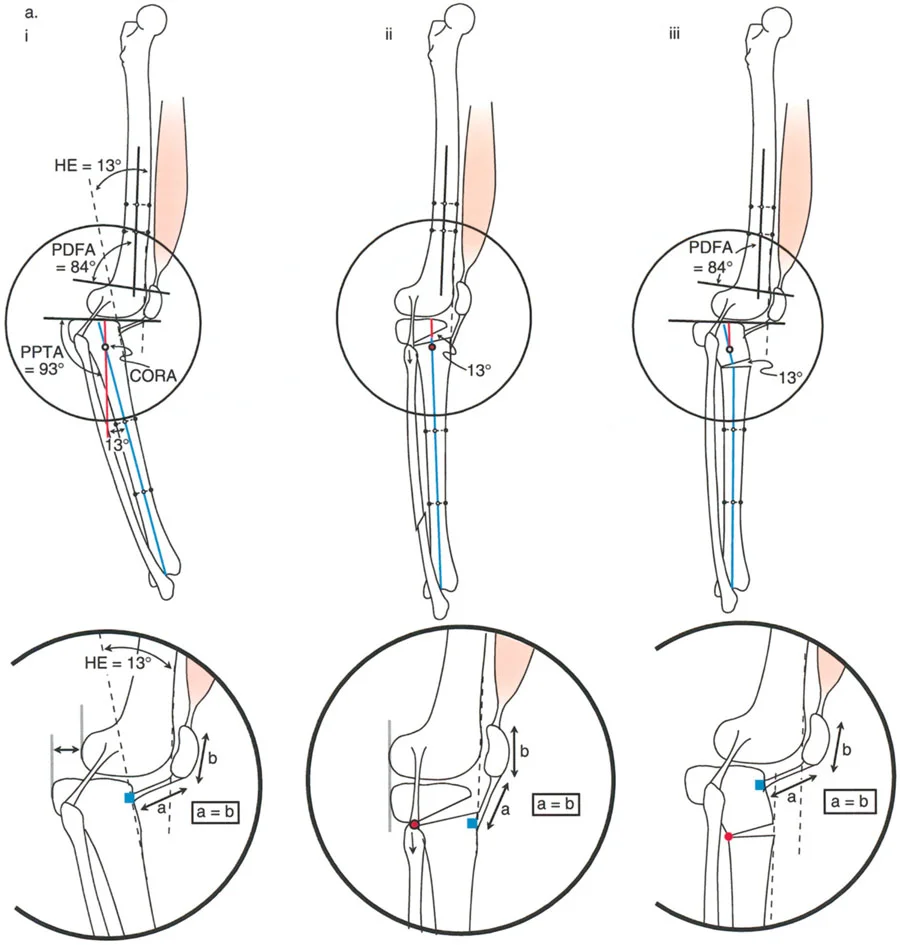

في المستوى السهمي، يجب أن تكون هناك زوايا محددة بين محاور العظام وخطوط المفصل لضمان توزيع متوازن للوزن واستقرار الأربطة. هذه الزوايا هي حجر الزاوية في مبادئ الدكتور بالي لتصحيح التشوهات:

- زاوية الفخذ الخلفية البعيدة (PDFA): وهي الزاوية بين المحور التشريحي لعظم الفخذ وخط مفصل الفخذ البعيد في المستوى السهمي. قيمتها الطبيعية حوالي 83 درجة.

- زاوية الظنبوب الخلفية القريبة (PPTA): وهي الزاوية بين المحور التشريحي لعظم الظنبوب وهضبة الظنبوب. تتراوح قيمتها الطبيعية بين 81 و 84 درجة.

يتطلب التخطيط السليم تحديد خطوط العظام الطويلة وحساب قمة التشوه بدقة. وكما هو الحال في مبادئ محاذاة المحور، فإن تحديد خطوط منتصف العظم بالنسبة لخطوط توجيه المفصل هو الخطوة الأولى في تحديد مركز دوران الانحراف (CORA)، وهو النقطة التي يجب أن يتم عندها قطع العظم لتصحيح التشوه.

عند تصحيح تشوه التقوس الأمامي، يجب على الجراح حساب مركز دوران الانحراف (CORA) بعناية. غالباً ما يكون التشوه قريباً جداً من المفصل، مما يجعل تثبيت العظم بعد القطع أمراً صعباً.

عند التخطيط لقطع العظم لتصحيح التقوس الخلفي في الظنبوب، فإن موقع القطع العظمي بالنسبة للحدبة الظنبوبية هو القرار الأكثر أهمية الذي سيتخذه الجراح. فالنتائج الميكانيكية الحيوية لهذا الاختيار تحدد ما إذا كان خلع الركبة الجزئي سيتم تقليله أو تفاقمه بشكل كارثي.

قطع العظم فوق الحدبة الظنبوبية (النهج المفضل)

عندما يوجد تشوه تقوس خلفي مع وجود الحدبة الظنبوبية بالقرب من خط المفصل، فإن قطع العظم على شكل إسفين فتح فوق الحدبة الظنبوبية يكون مفيداً للغاية ويمثل المعيار الذهبي في مبادئ بالي لإعادة البناء.

- آلية العمل: يؤدي فتح إسفين عند هذا المستوى المحدد إلى تصحيح محاذاة العظم التقوسية، واستعادة زاوية PPTA الطبيعية (81-84 درجة) مباشرة.

- تقليل المفصل غير المباشر: نظراً لأن الحدبة الظنبوبية تبقى على الجزء البعيد من قطع العظم، فإن فتح الإسفين للأمام يسحب وتر الرضفة جسدياً. يعمل هذا الشد كحزام تقليل داخلي، يسحب كامل ساق الظنبوب وهضبة الظنبوب للأمام، وبالتالي يقلل بشكل غير مباشر الخلع الجزئي الخلفي للمفصل الظنبوبي الفخذي.

- منع انخفاض الرضفة: قد يفترض المرء أن سحب الحدبة الظنبوبية للأسفل سيسبب انخفاضاً في الرضفة. ومع ذلك، نظراً لأن كامل الظنبوب يتحرك للأمام وتتغير زاوية المفصل، فإن انخفاض الرضفة الثانوي لا يحدث. يتم الحفاظ على المسافة النسبية بين الرضفة وخط المفصل.

- نقل الشظية: يمكن أن يساعد نقل الشظية للأسفل أيضاً في تقليل الخلع الجزئي الخلفي. نظراً لأن الرباط الجانبي الوحشي (LCL) موجه في اتجاه أمامي خلفي، فإن سحب الشظية للأسفل يشد الرباط الجانبي الوحشي، مما يساعد في الترجمة الأمامية للظنبوب.